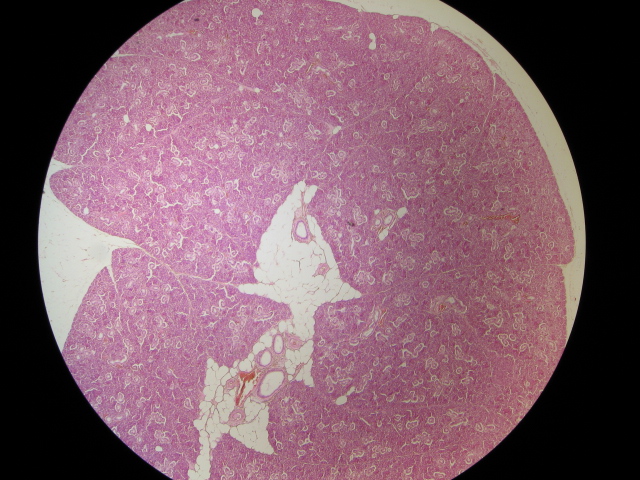

Identify this accessory organ,  | liver |